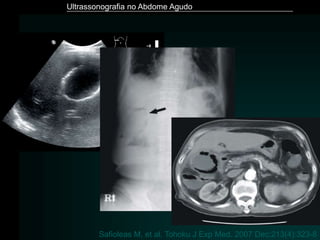

Safioleas M, et al. Tohoku J Exp Med. 2007 Dec;213(4):323-8

Ultrassonografia no AbdomeAgudo Safioleas M, et al. Tohoku J Exp Med. 2007 Dec;213(4):323-8